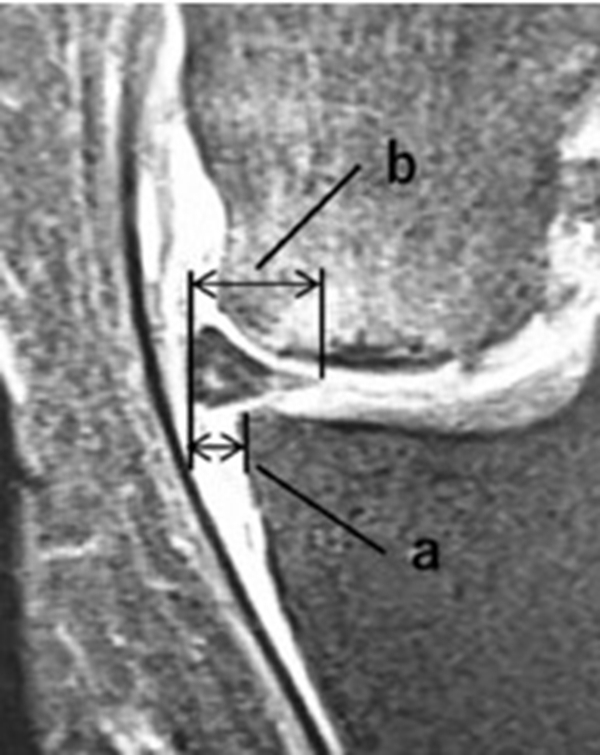

内侧半月板挤压(MME)以绝对值和挤压相对百分比 (RPE) 的形式呈现,其定义为挤压半月板宽度与整个半月板宽度相比的百分比